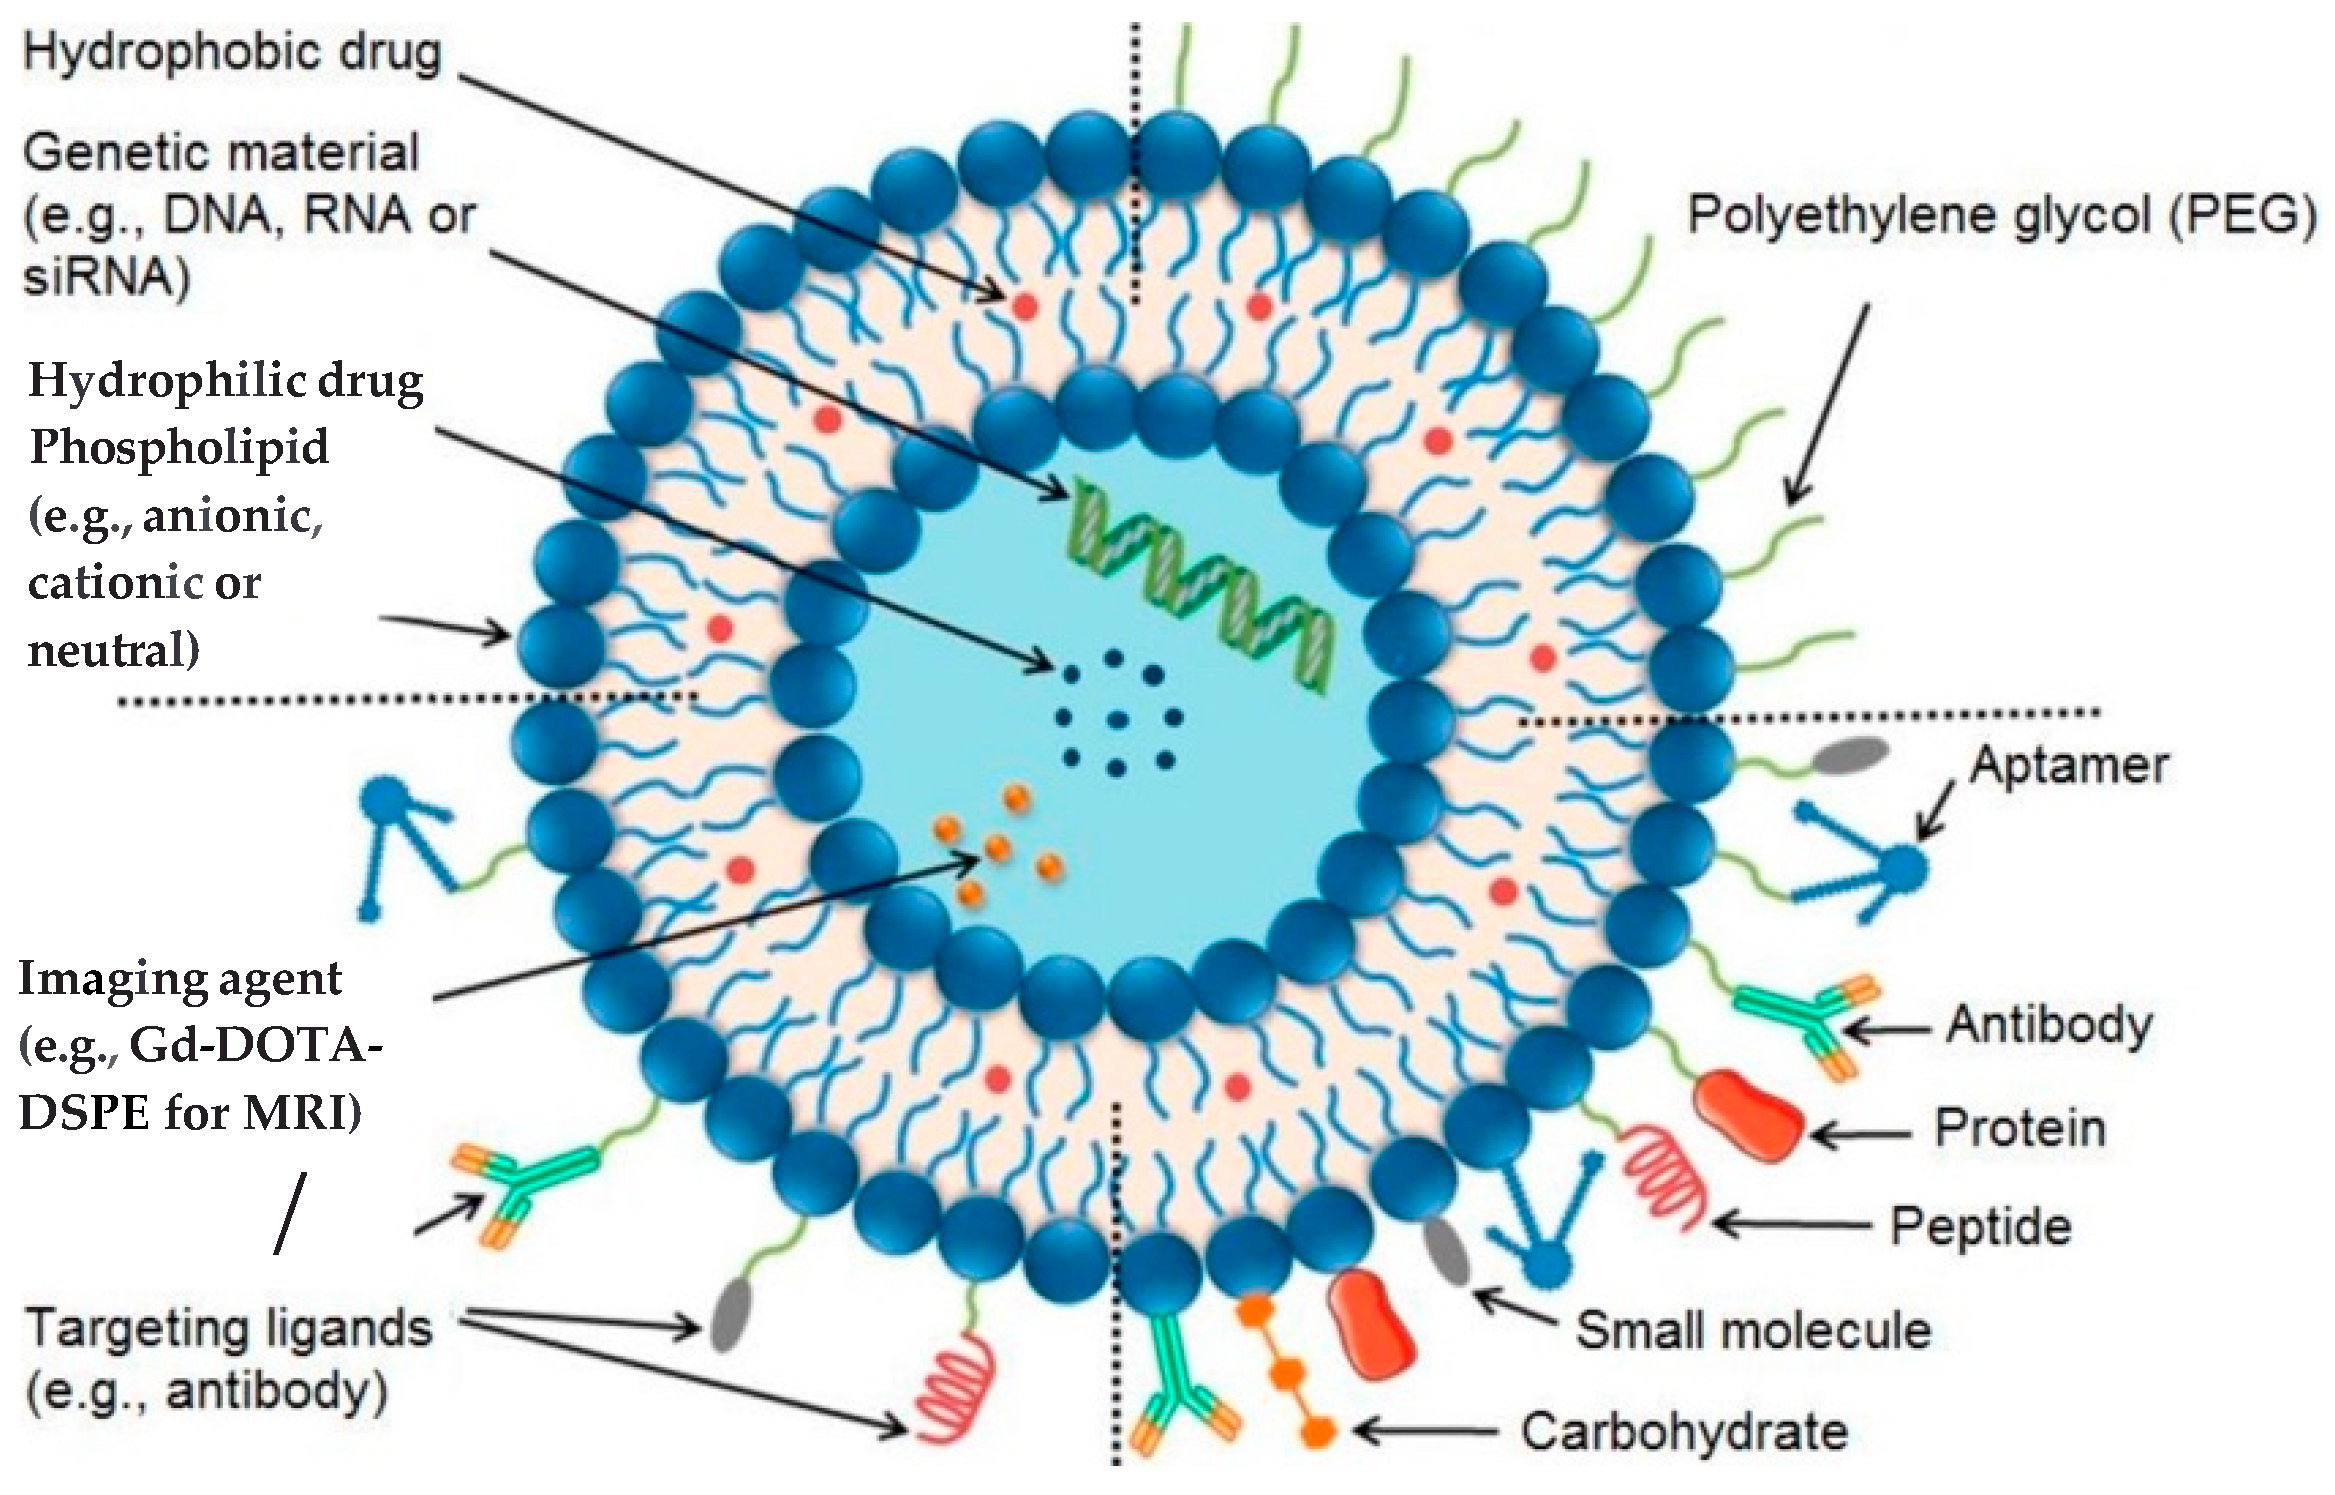

4. Liposomes and Therapeutic Strategies

5. Liposomes as an Imaging Agent for Bone Implants

6. Liposomes Detect Oxidative Stress and Enhance the Bone-Healing Process